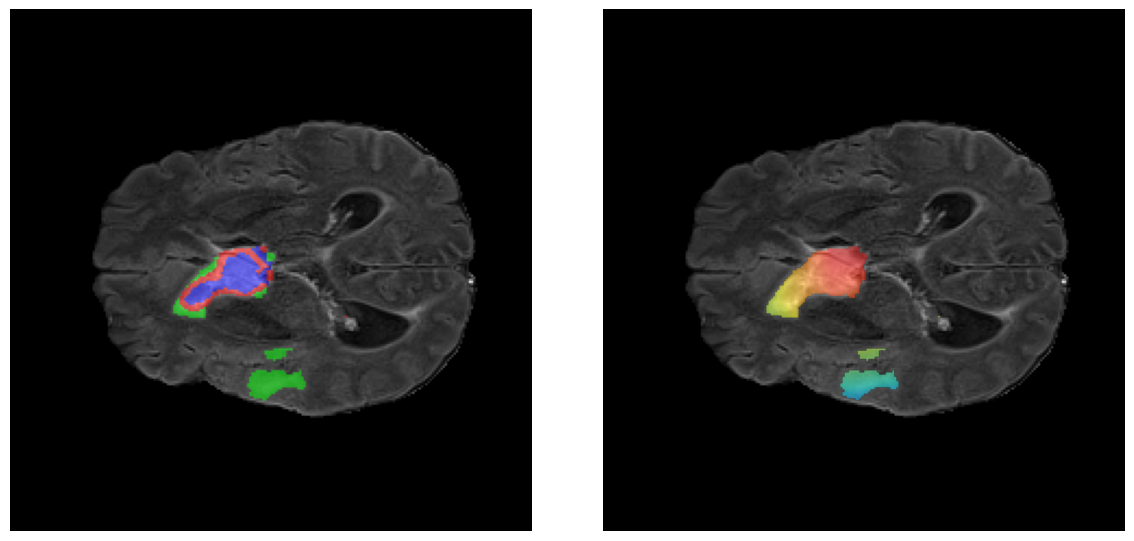

Mapas de Explicabilidad (Grad-CAM++)

Visualización de las regiones de atención del modelo que validan su razonamiento clínicamente relevante

Ejemplos HGG - Atención en Núcleo Necrótico y Tumor Realzado

HGG Grad-CAM++ 1 HGG Grad-CAM++ 2 HGG Grad-CAM++ 3 HGG Grad-CAM++ 4 HGG Grad-CAM++ 5 HGG Grad-CAM++ 6

Los heatmaps muestran que el modelo concentra su atención en las regiones de Tumor Realzado (rojo) y Núcleo Necrótico (azul), características patológicas clave de los gliomas de alto grado.

Ejemplos LGG - Atención Difusa en Edema Peritumoral

LGG Grad-CAM++ 1 LGG Grad-CAM++ 2 LGG Grad-CAM++ 3 LGG Grad-CAM++ 4 LGG Grad-CAM++ 5 LGG Grad-CAM++ 6

Para casos LGG, la atención del modelo es más difusa y se concentra principalmente en la región de Edema Peritumoral (verde), consistente con la naturaleza más infiltrativa y menos agresiva de estos tumores.